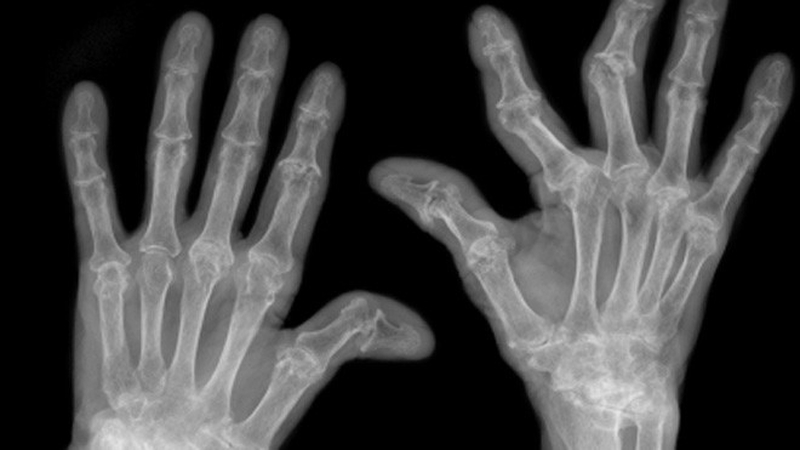

Chụp X - quang

Phương pháp này giúp phát hiện được hình ảnh lắng đọng tinh thể urat tại sụn khớp ở những cơn gout cấp đầu tiên hoặc ngay cả khi chưa có triệu chứng lâm sàng. Chụp X - quang có thể phát hiện sớm các biến đổi ở phần mềm, sụn khớp và xương do bệnh gout gây ra như hạt tophi, hình ảnh khuyết xương, lắng đọng tinh thể urat trên bề mặt sụn khớp, tràn dịch khớp.